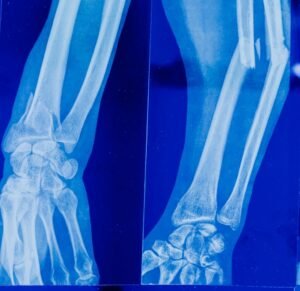

A cirurgia da mão é uma especialidade médica dedicada ao diagnóstico e tratamento de lesões, doenças e deformidades que acometem as mãos, punhos, antebraços e cotovelos, pois essas estruturas são essenciais em praticamente todas as atividades diárias. Por causa de sua alta exigência funcional, condições como tendinites, fraturas, síndrome do túnel do carpo e lesões por esforço repetitivo (LER) tornaram-se cada vez mais frequentes.

Quando o tratamento clínico não é suficiente para aliviar a dor ou recuperar a função, a cirurgia da mão pode ser indicada. Os procedimentos podem envolver reparo de tendões, nervos, ossos, ligamentos, liberação de estruturas comprimidas, correção de deformidades e reconstruções complexas, muitas vezes utilizando técnicas de microcirurgia, que permitem maior precisão e melhores resultados funcionais; contudo, cada casa é avaliado de forma individualizada.

Fraturas e Luxações

Atendimento ortopédico para traumas recentes, com foco em preservar a função e acelerar a recuperação.